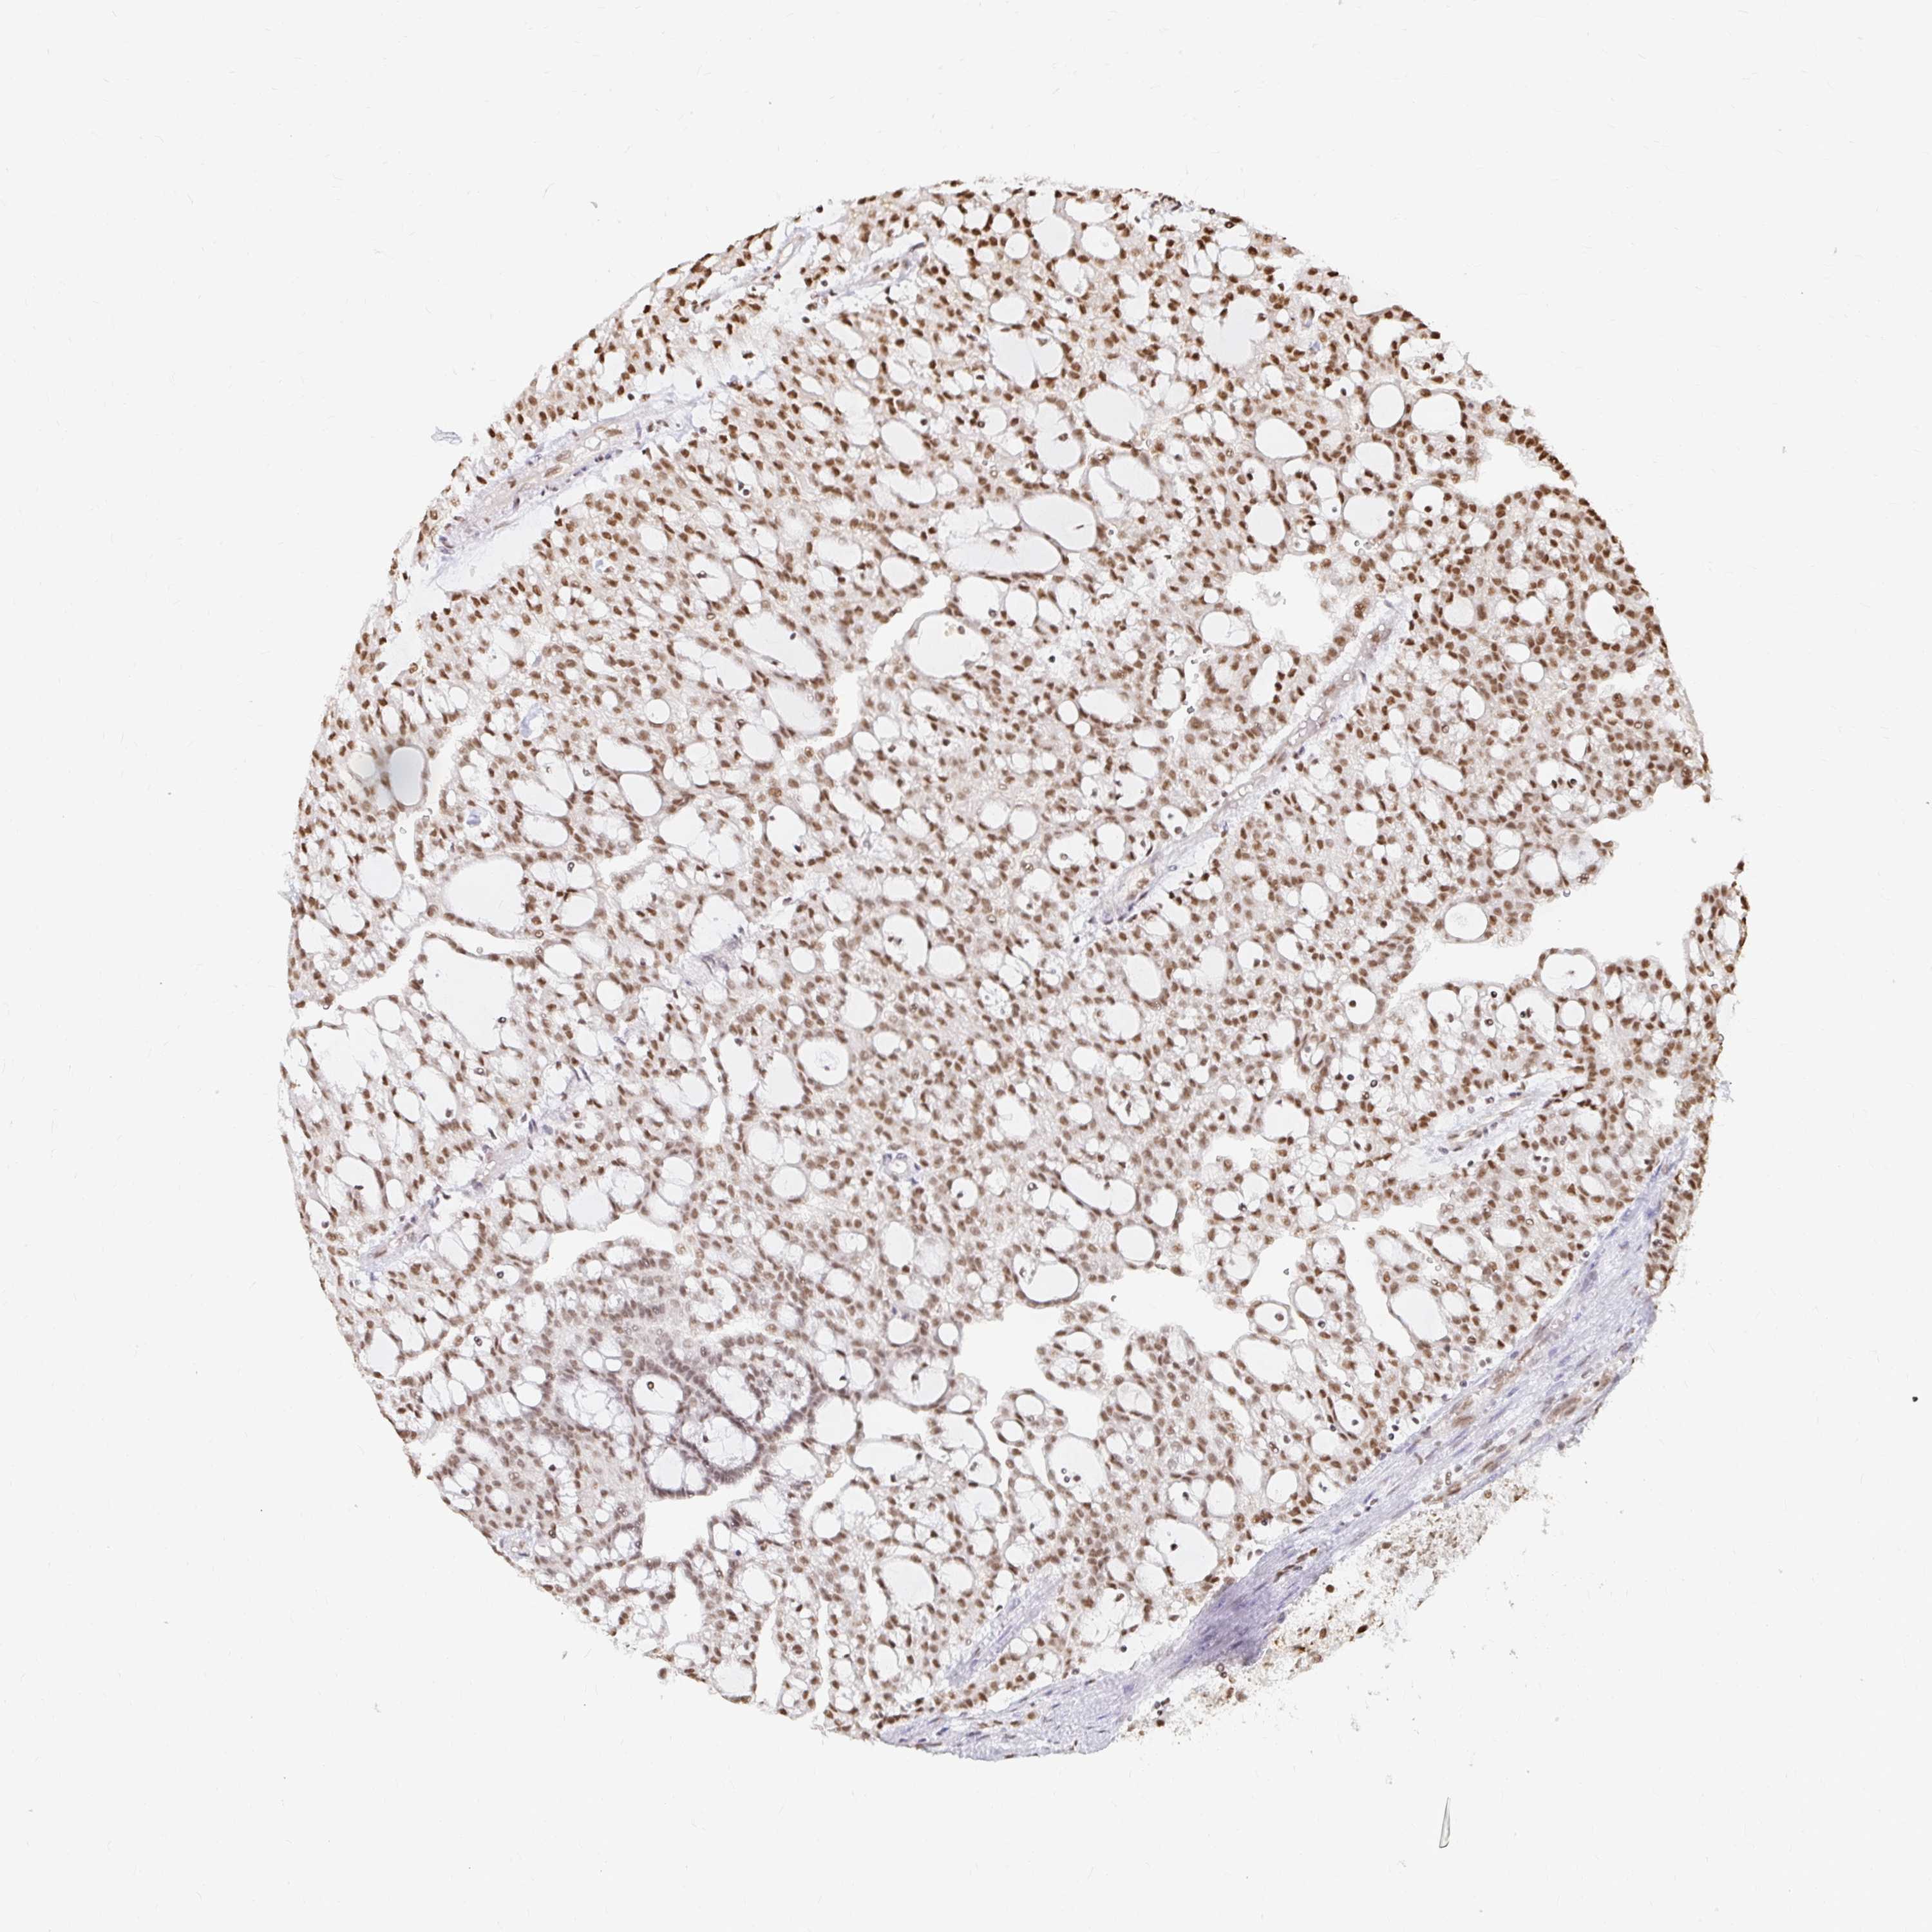

KIDNEY RENAL CLEAR CELL CARCINOMA (TCGA) - Interactive survival scatter ploti

The Survival Scatter plot shows the clinical status (i.e. dead or alive) for all individuals in the patient cohort, based on the same data that underlies the corresponding Kaplan-Meier plots. Patients that are alive at last time for follow-up are shown in blue and patients who have died during the study are shown in red.

The x-axis shows the expression levels (FPKM) of the investigated gene in the tumor tissue at the time of diagnosis. The y-axis shows the follow-up time after diagnosis (years). Both axes are complimented with kernel density curves demonstrating the data density over the axes. The top density plot shows the expression levels (FPKM) distribution among dead (red) and alive patients (blue). The right density plot shows the data density of the survived years of dead patients with high and low expression levels respectively, stratified using the cutoff indicated by the vertical dashed line through the Survival Scatter plot. This cutoff is automatically defined based on the FPKM cutoff that minimizes the p-score. The cutoff can be changed by dragging the vertical line or by entering a cutoff value in the square labeled "Current cut-off".

Under the Survival Scatter plot the p-score landscape (black curve; left axis) is shown together with dead median separation (red curve; right axis). Dead median separation is the difference in median mRNA expression between patients who have died with high and low expression, respectively. It is calculated as follows: median FPKM expression of dead patients with high expression - median FPKM expression of dead patients with low expression. This is intended to aid the user in visually exploring custom cutoffs and the associated p-scores and dead median separation.

Individual patient data is displayed and can be filtered by clicking on one or more of the category buttons on the top of the page. Categories describing expression level and patient information include: high, low, alive, dead, female, male and tumor stages. The scale of the x-axis can be toggled between linear and log-scale by clicking on the "x log" button. Mouse-over function shows TCGA ID, patient information and mRNA expression (FPKM) for each patient.

& Survival analysisi

Kaplan-Meier plots summarize results from analysis of correlation between mRNA expression level and patient survival. Patients were divided based on level of expression into one of the two groups "low" (under cut off) or "high" (over cut off). X-axis shows time for survival (years) and y-axis shows the probability of survival, where 1.0 corresponds to 100 percent.

HNRNPU is potential prognostic, high expression is favorable in Kidney Renal Clear Cell Carcinoma (TCGA)

Best expression cut offi

Based on the FPKM value of each gene, patients were classified into two groups and association between prognosis (survival) and gene expression (FPKM) was examined. The best expression cut-off refers the FPKM value that yields maximal difference with regard to survival between the two groups at the lowest log-rank P-value. Best expression cut-off was selected based on survival analysis .

When clicking on this number, the vertical dashed line indicating cut-off, the interactive survival plot, and the Kaplan-Meier curve will be adjusted to show results based on the best expression cut-off.

: 166.47

TCGA RNA samplesi

RNA-seq data is reported as average FPKM (number Fragments Per Kilobase of exon per Million reads), generated by the The Cancer Genome Atlas (TCGA) .

Normal distribution across the dataset is visualized with box plots, shown as median and 25th and 75th percentiles. Points are displayed as outliers if they are above or below 1.5 times the interquartile range. FPKM values of the individual samples are presented next to the box plot.

Average pTPM 137.9

Number of samples 521